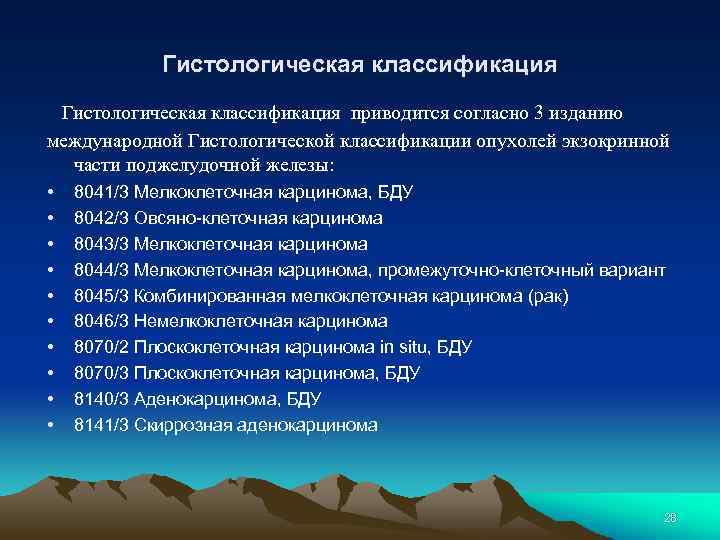

Гистологическая классификация приводится согласно 3 изданию международной Гистологической классификации опухолей экзокринной части поджелудочной железы: • • • 8041/3 Мелкоклеточная карцинома, БДУ 8042/3 Овсяно-клеточная карцинома 8043/3 Мелкоклеточная карцинома 8044/3 Мелкоклеточная карцинома, промежуточно-клеточный вариант 8045/3 Комбинированная мелкоклеточная карцинома (рак) 8046/3 Немелкоклеточная карцинома 8070/2 Плоскоклеточная карцинома in situ, БДУ 8070/3 Плоскоклеточная карцинома, БДУ 8140/3 Аденокарцинома, БДУ 8141/3 Скиррозная аденокарцинома 28